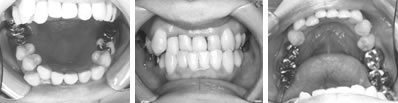

取り外しのできる簡単な装置で治療した例

各種検査で確認をした後に、上顎前歯を外に出すことが適当と判断された症例です。本人の性格やご家族の方の希望も考慮して治療方針が決定されます。取り外しのできる簡単な装置を用いて治療を開始しました。